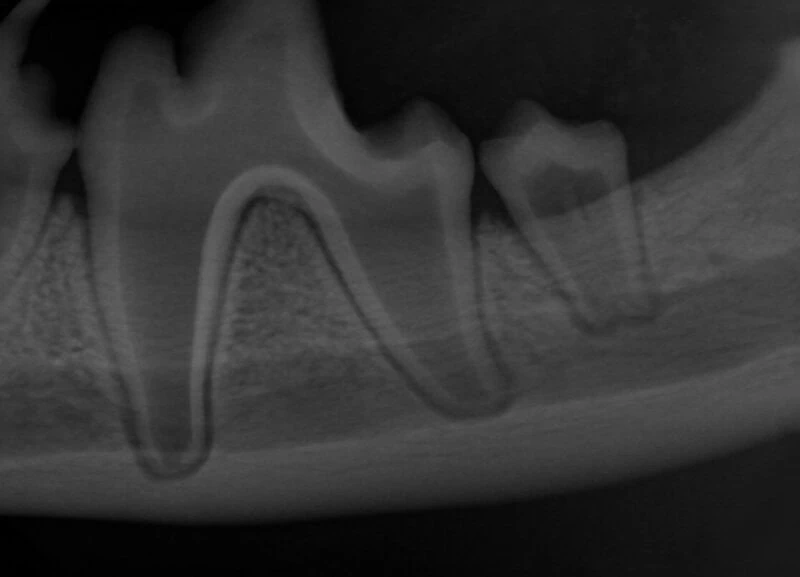

A relaxed and interactive online learning session focused on improving confidence in interpreting dental radiographs in small animal practice.

Each session will review real clinical cases, discussing radiographic findings, common pitfalls, and practical tips for everyday dentistry. We will also include discussion of evidence-based treatment options and clinical decision making.